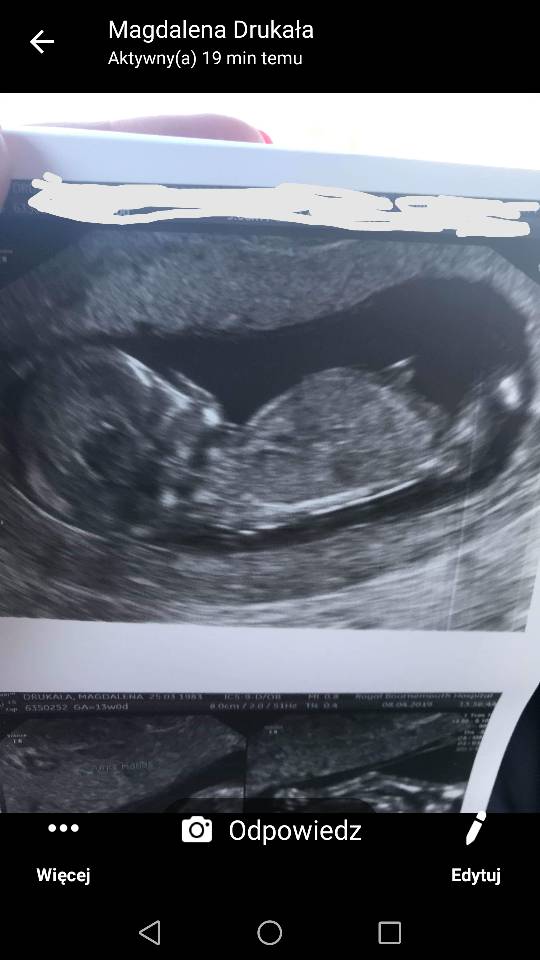

Usg chłopak czy dziewczynka

Witam w 19 tygodniu ciąży dowiedziałam się ze będę miała dziewczynkę w 20 tyg okazało się jednak , że to chłopak. Sama już nie wiem bo na jednym usg widać na pewno dziewuche a na drugim chłopca. Może to pempowina ?? Może ktoś mi pomoże rozwiązać ta zagadkę

Załączniki

• 4A8F5FF1-76CA-4DE0-AC12-5EDF08E820F2.jpg

4A8F5FF1-76CA-4DE0-AC12-5EDF08E820F2.jpg

596,4 KB · Wyświetleń: 44 148